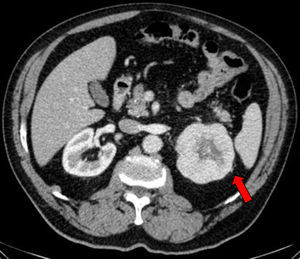

Caso clínicoSe trata de un varón obeso de 67 años de edad, con antecedentes de hipertensión arterial y enfermedad pulmonar obstructiva crónica en tratamiento y con buena estabilidad clínica. Acudió a consulta externa de reumatología por presentar un cuadro de dolor lumbar bajo de características mecánicas, así como también parestesias de moderada intensidad en la cara anterolateral de muslo izquierdo, de 3 meses de evolución, que se exacerbaban con la bipedestación prolongada y cedían con el reposo; negó algún otro síntoma asociado. En el examen físico destacó un abdomen globuloso, ausencia de dolor a la presión en las apófisis espinosas de todo el componente axial, maniobras radiculares negativas y exploración de cadera dentro de la normalidad, siendo el diagnóstico clínico compatible con una MP. Dado que las radiografías de columna y de caderas no mostraron alteraciones significativas, se solicitaron una analítica y una tomografía abdominal para completar los estudios. Los resultados del hemograma, la bioquímica, los marcadores tumorales y el examen de orina estuvieron dentro de lo normal; sin embargo, en la tomografía computarizada se objetivó una masa de 79mm en el polo superior del riñón izquierdo, con centro necrótico y posibles focos de invasión grasa perirrenal en su margen superior, sospechosa de neoplasia, sin otra afectación ni adenopatías patológicas (fig. 1). A continuación, se remitió el paciente al Servicio de Urología, procediéndose a una nefrectomía izquierda, con evolución favorable en el postoperatorio. Posteriormente, el paciente cursó con desaparición del dolor lumbar y las parestesias. La pieza quirúrgica fue enviada para el estudio anatomopatológico, siendo los hallazgos histológicos una proliferación sólida de células monomorfas con escasa atipia nuclear y amplio citoplasma eosinófilo de límites definidos, todo ello compatible con un oncocitoma renal (fig. 2).

La lesión por compresión del nervio femorocutáneo está favorecida por su largo recorrido y las características anatómicas particulares, siendo más frecuente las producidas a nivel inguinal, originadas por compresión externa por el uso de cinturones, ropa ajustad, un abdomen globuloso9 o por la presencia de alteraciones anatómicas como lipomas localizados a ese nivel10. Asimismo, se han descrito casos de MP secundarios a compresión del nervio femorocutáneo a nivel intraabdominal originadas por masas retroperitoneales, como las ocasionadas por la presencia de hematomas, seudoaneurismas11 o tumores de partes blandas u óseos4,12. En el presente caso, tras el estudio con pruebas de imagen, se objetivó una tumoración renal de gran tamaño y características patológicas, por lo que ante la sospecha de malignidad se decidió realizar una nefrectomía radical izquierda, obteniendo como resultado anatomopatológico un oncocitoma renal bien diferenciado. Posteriormente, nuestro paciente cursó con buena evolución clínica y desaparición de su sintomatología. Si bien el oncocitoma renal es una neoplasia benigna que constituye una lesión rara del riñón (del 3 a 6% de todas las neoplasias renales), clínica y radiológicamente es indistinguible del carcinoma de células renales, por lo que su diagnóstico definitivo es solo mediante su estudio histológico; los oncocitomas suelen ser asintomáticos (del 58 al 83%), aunque en algunas ocasiones pueden comenzar con hematuria, dolor lumbar o síntomas provocados por su efecto de masa retroperitoneal. Por todas estas incertidumbres acerca del diagnóstico preoperatorio, la mayoría de los autores han señalado la necesidad de tratar a estos tumores en forma enérgica, con ablación térmica, nefrectomía parcial o nefrectomía radical, de acuerdo con las circunstancias clínicas individuales13.

ConclusionesNuestro caso clínico ilustra una presentación de MP en un paciente obeso con características suficientes que podrían haber justificado dicha neuropatía; sin embargo, tras profundizar los estudios con el fin de descartar otras causas que podrían provocar lesión y/o atrapamiento en algún punto del recorrido del nervio femorocutáneo, se objetivó una tumoración renal izquierda con un centro necrótico, por lo que ante la sospecha de malignidad de procedió a un tratamiento radical, con buena evolución posterior.